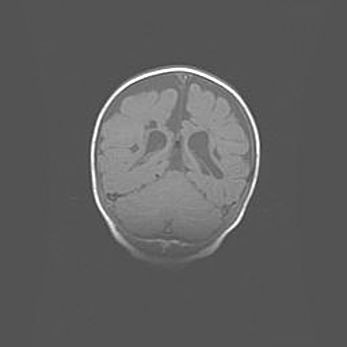

Церебральная ишемия II.

Возраст: 5 дней

Вес: 3400 г

Пол: женский

Окружность головы: 35 см

Срок гестации: 39 недель

Церебральная ишемия – это заболевание, характеризующееся недостаточностью (гипоксией) либо полным прекращением (аноксией) снабжения мозга кислородом по причине закупорки одного или нескольких сосудов. Это приводит к  что метаболическим расстройствам различной степени тяжести в тканях головного мозга, развитию коагуляционных некрозов и гибели нейронов.